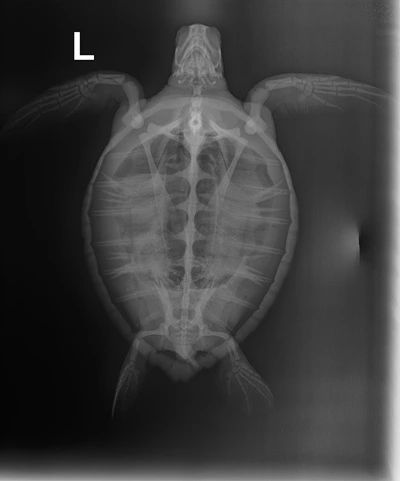

1.60 kg juvenile Atlantic Green sea turtle

Head/Flippers/Soft Tissue: 1 small abrasion on the left front flipper

In House PCV: 34%, TS: 4.0 , Glucose: 90

Meds administered: Ceftaz (antibiotic) , VitB (appetite stimulant) & Normosol